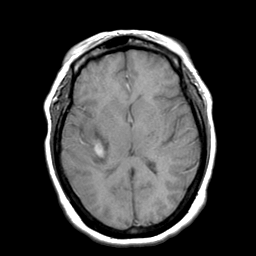

Cerebral hemorrhage, MR Study mr-t1 -- Slice #13

[Home][Help][Clinical] Slice 13